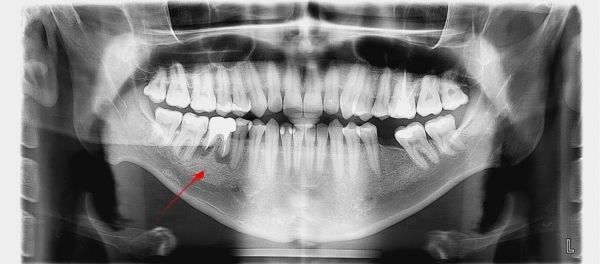

Добрый день. Мне в стоматологии сделали снимок зуба и сказали, что зуб надо удалять, так как вылечить не получится. Подскажите, так ли это? Может стоит обратиться к другим врачам? (фото зуба выслала на e-mail). Зуб № 46. На данный момент зуб не беспокоит. Три месяца назад был флюс, после разреза всё прошло. Антибиотиками не лечила, так как беременность. Сейчас срок 17 недель. Спасибо!

Да, к сожалению зуб необходимо удалить, так как на верхушках всех корней наблюдается обширное воспаление.